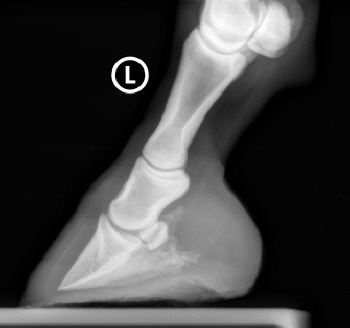

Röntgenbilder akuter- und chronischer Hufrehehufe vorher und nachher

Nachstehend stellen wir einige Röntgenbilder von Hufrehepferden ins Netz, welche das Vorher und das Nachher zeigen. Wir möchten damit aufzeigen, dass durch eine richtige Hufbearbeitung ein Hufbein wieder in eine korrekte Lage innerhalb der Hornkapsel zu liegen kommen kann.

In besonders schweren Fällen wurde doch zumindest eine Optimierung angestrebt.

vorher